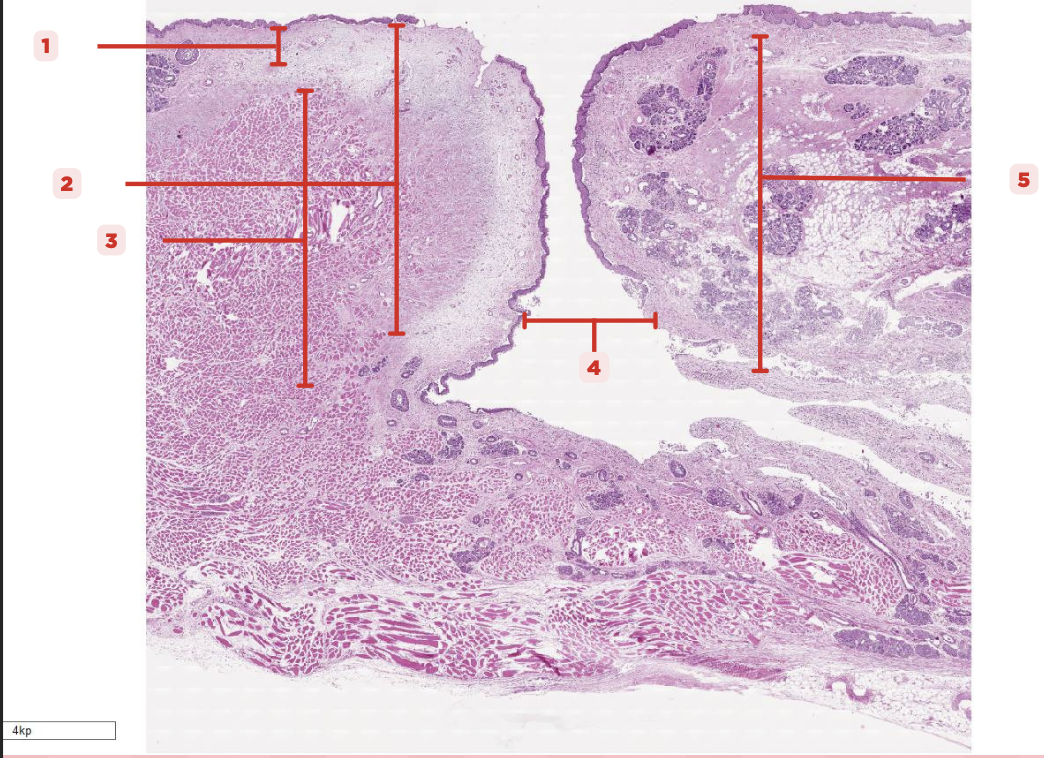

Respiratory Epithelium

Identify the structure labeled as 1.

Lamina Propria

Identify the structure labeled as 2.

Bony spicule

Identify the structure labeled as 3.

Respiratory Epithelium

What epithelium lines this structure?

Ciliated pseudostratified epithelium

What type of epithelium lines this structure?

Respiratory Epithelium

Identify the structure labeled as 1.

Mucosa

Identify the structure labeled as 2.

Bone

Identify the structure labeled as 3.

Keratinized stratified squamous epithelium

What’s the lining epithelium at #3?

No

Are Glands present at #1?

Lamina Propria

Identify the structure labeled as 1.

Adipocytes

Identify the structure labeled as 2.

Keratinized stratified squamous epithelium

Identify the structure labeled as 3.